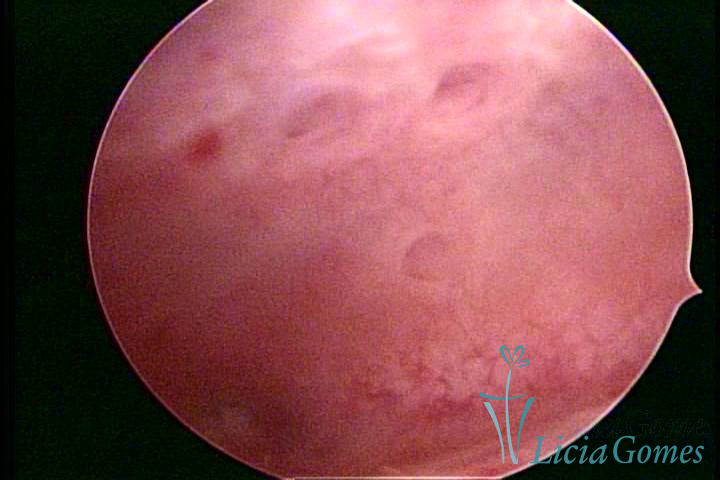

ADENOMYOSIS

The presence of endometrial tissue on the muscular layer of the uterus.

Video hysteroscopy allows diagnosing the lesions next to the superficial myometrial layers next to the endometrium, allowing the view of in situ, purplish, or chocolate brown lesions.